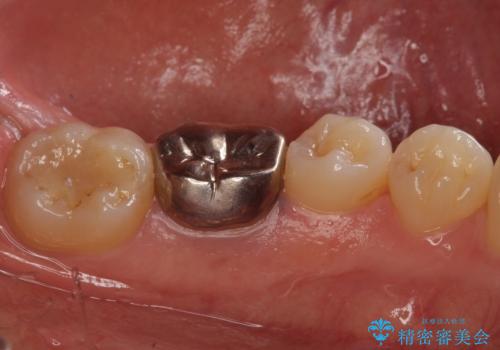

- 右下の奥歯に入れた銀歯を白くしたいとのことで来院されました。

根っこの治療がされていますが、症状もなくレントゲン画像で病変も確認できないため根管内には触れず被せ物のやり替えのみとなりました。

下の奥歯は口を開くと簡単に外から見えてしまいます。

銀色だった歯が白くなったことで大変喜んでいただけました。